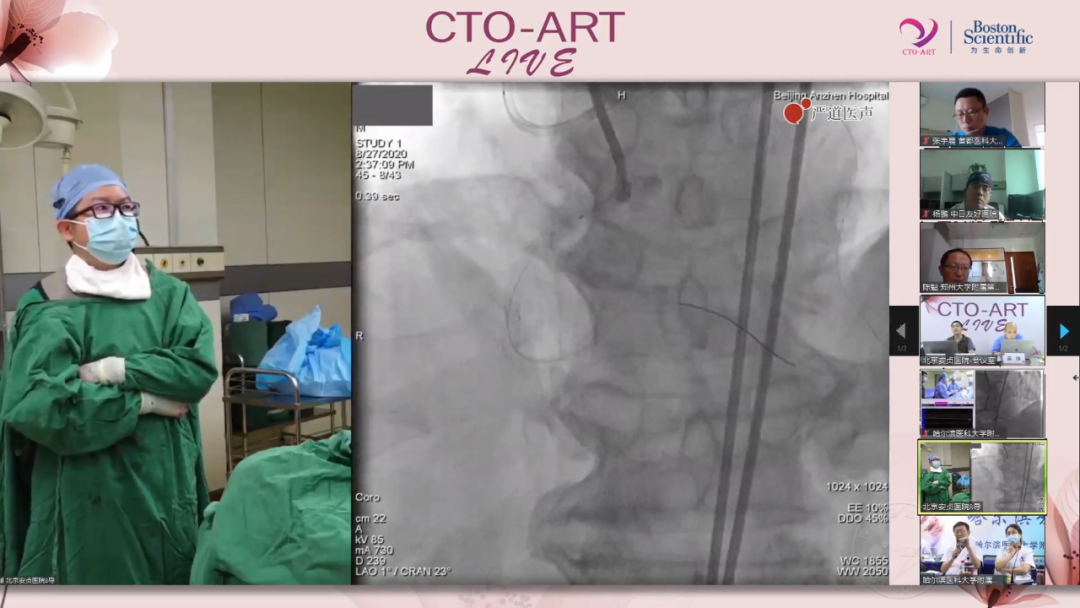

CTO ART作为CTO介入治疗领域的盛会,为越来越多的介入治疗医师提供了学习交流平台。正如大会主席柳景华教授所说,ART不仅是Antegrade & Retrograde Therapeutics的缩写,更是代表CTO PCI术者的匠心精神,它不仅是一场手术,更是无数的CTO术者用心打磨出的艺术品。虽然本期的CTO ART LIVE会议已经落下帷幕,但是学术的探讨交流永不停歇,期待金秋十月ADR专场尽快与大家见面!